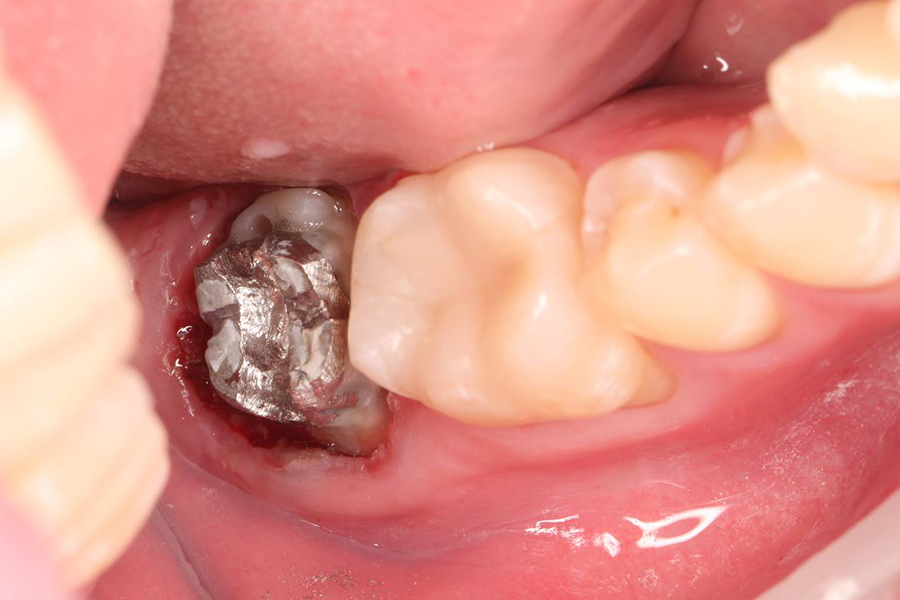

Лечение асимптоматического периодонтита

ЖалобыПлановое перелечивание перед ортодонтическим лечением

Лечение

Использована туннельная техника — малотравматичный подход, при котором:

1. сохраняется кровоснабжение тканей,

2. нет вертикальных разрезов, такой подход обеспечивает предсказуемое заживление и высокую эстетичность результата без заметных рубцов.